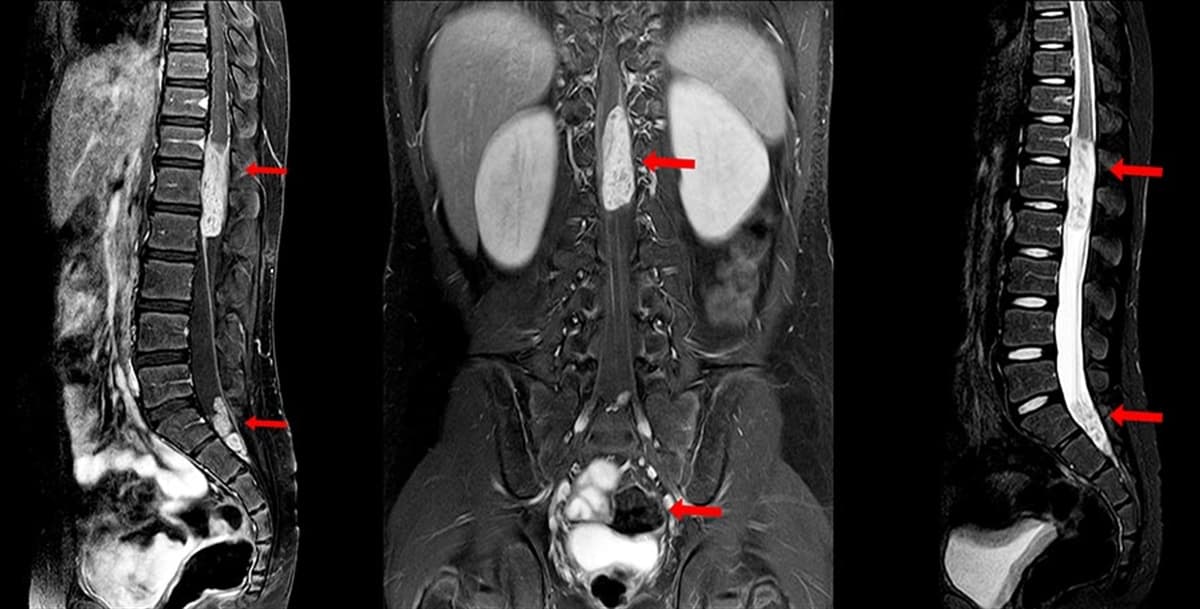

- MRI ile omurgada, omurilikte ve sinirlerde ortaya çıkabilecek tümörü görüntüler ve buradan yola çıkarak teşhis koyar.